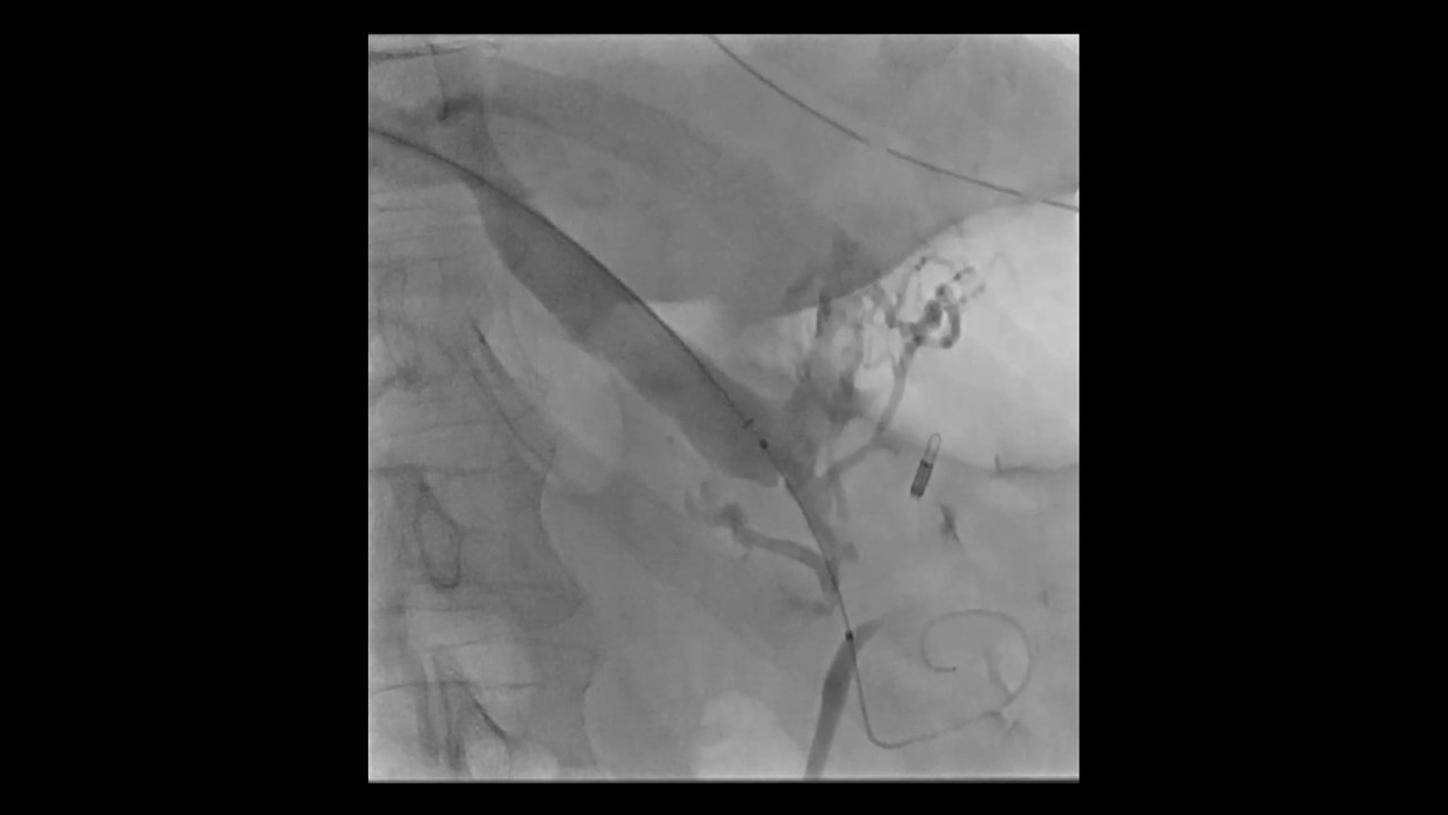

with OPTIQ AIOPTIQ AI delivers constant image quality* defined by CNR independent of C-arm angulation and patient size - in support of the ALARA10 principle throughout the procedure. And it optimizes device visibility based on the X-ray absorption properties of the respective material.

On top, an AI-powered algorithm reduces image noise in real time while better preserving structures11,12 across all 2D imaging modes and different body regions.